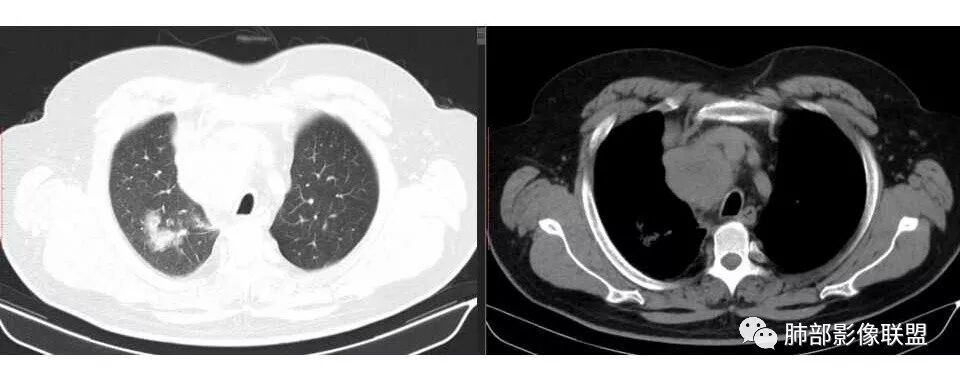

支气管狭窄,壁有侵犯

局限性中央间质增厚,考虑癌性淋巴管炎

部分区域有结节感

右侧胸膜增厚

1.右肺上叶不规则结节影,右肺门及纵隔多结节并形成巨大块影,密度均匀,沿途支气管明显狭窄。

原发灶小或隐匿,肺门纵隔淋巴结异常增大,所谓“娘小崽大”常见于肺小细胞癌!

2.右肺小叶间隔增厚伴微小结节,提示癌性淋巴管炎。